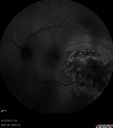

FLUORESCEIN ANGIOGRAPHY: Fluorescein angiography of the left eye shows early hypofluorescence and hyperfluorescence around the area of the choroidal mass in the left eye with filling of what looks to be its own vasculature. In the later frames of the angiogram, there is a rim of hypofluorescence around it, where there is mottled pigment and then some hyperfluorescence within the lesion. The lesion does appear to have two components, one of which is a circular area in the center and then a more diffuse area around the periphery.

INDOCYANINE GREEN ANGIOGRAPHY: Indocyanine green angiogram of the left eye was obtained, which does show hypofluorescence in the area of the lesion. There do appear to be some vessels within the lesion, but only minimally.